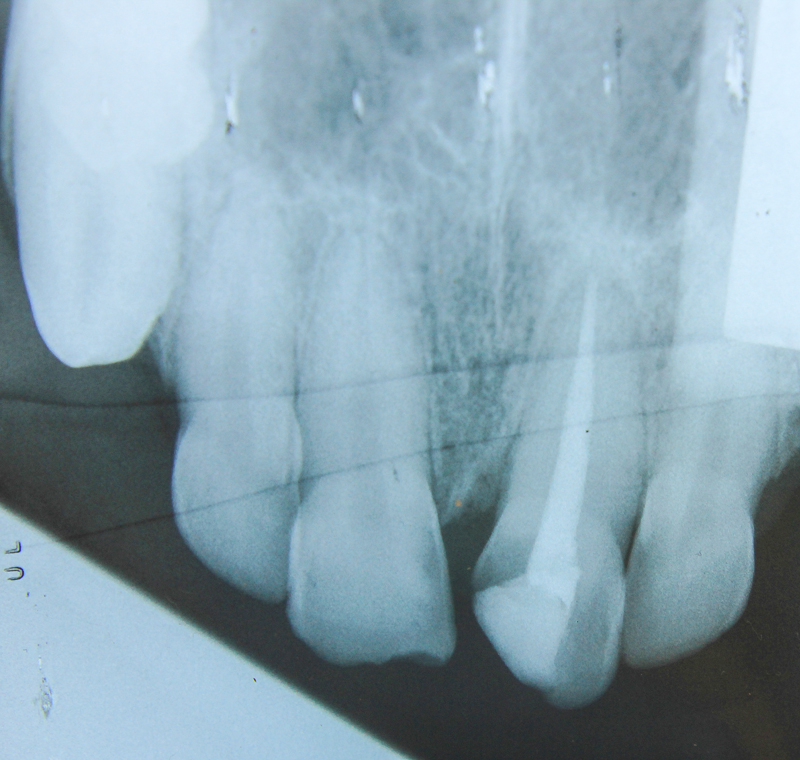

Preoperative radiograph. Note large diameter canine root canal in this young animal

Working length radiograph, 40 mm